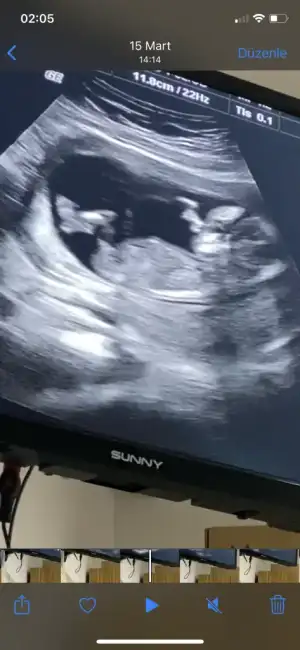

Merhaba 11+4de size usg atmıştım kız gibi demistiniz şimdi 14+5 atıyorum tekrar yorumlarmısiniz hala söylemedi doktorErkek görünüyor

11+4 de kız demiştim ama 14+5 de artık organı oluşmuş oluyor bakalım hayırlısı olsun tipi kız gibiMerhaba 11+4de size usg atmıştım kız gibi demistiniz şimdi 14+5 atıyorum tekrar yorumlarmısiniz hala söylemedi doktor

Merhaba, bebeğin cinsiyeti için erkek olabilir demiştiniz ve doğru tahmin etmişsiniz. Tahmininiz için teşekkür ediyorum :)En iyi 11 12 13 haftalar olmalı